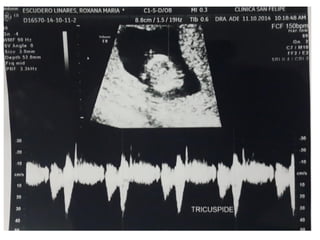

REGURGITACIÓN TRICÚSPIDEA

DUCTUS VENOSO

• Vaso pequeño que conecta la vena umbilical con la

proximidad de la aurícula derecha. Tiene un papel crítico

dirigiendo la sangre oxigenada al cerebro fetal

• Un 20% de la sangre oxigenada de la placenta sobrepasa el

hígado y se dirige al corazón fetal. Entra en la aurícula

derecha y luego a la izquierda, a través del foramen oval.

• De la aurícula izquierda pasa al ventrículo izquierdo y luego

a la aorta

VALORACIÓN DV

• Semanas 11+0-13+6 y la LCC entre 45-84 mm. El feto no

debe moverse.

• El tamaño de la imagen debe ser tal que el tórax y abdomen

fetal ocupen toda la pantalla. Se debe obtener un corte

sagital medio del tronco fetal.

• Se debe usar el Doppler color para demostrar la vena

umbilical, el ductus venoso y el corazón fetal. La ventana

del Doppler pulsado debe ser pequeña (0,5-1,0 mm) y debe

situarse en la zona de aliasing normalmente en amarillo

• El ángulo de insonación debe ser menor de 30 grados.

• El filtro debe ser de baja frecuencia (50-70 Hz), para

permitir la visualización de la onda completa.

• La velocidad de barrido debe ser alta (2-3 cm/s), para

obtener una forma más ancha y poder evaluar mejor la onda

A.

DUCTUS VENOSO • Vasopequeño que conecta la vena umbilical con la proximidad de la aurícula derecha. Tiene un papel crítico dirigiendo la sangre oxigenada al cerebro fetal • Un 20% de la sangre oxigenada de la placenta sobrepasa el hígado y se dirige al corazón fetal. Entra en la aurícula derecha y luego a la izquierda, a través del foramen oval. • De la aurícula izquierda pasa al ventrículo izquierdo y luego a la aorta

VALORACIÓN DV • Semanas11+0-13+6 y la LCC entre 45-84 mm. El feto no debe moverse. • El tamaño de la imagen debe ser tal que el tórax y abdomen fetal ocupen toda la pantalla. Se debe obtener un corte sagital medio del tronco fetal. • Se debe usar el Doppler color para demostrar la vena umbilical, el ductus venoso y el corazón fetal. La ventana del Doppler pulsado debe ser pequeña (0,5-1,0 mm) y debe situarse en la zona de aliasing normalmente en amarillo

VALORACIÓN DV • Elángulo de insonación debe ser menor de 30 grados. • El filtro debe ser de baja frecuencia (50-70 Hz), para permitir la visualización de la onda completa. • La velocidad de barrido debe ser alta (2-3 cm/s), para obtener una forma más ancha y poder evaluar mejor la onda A.